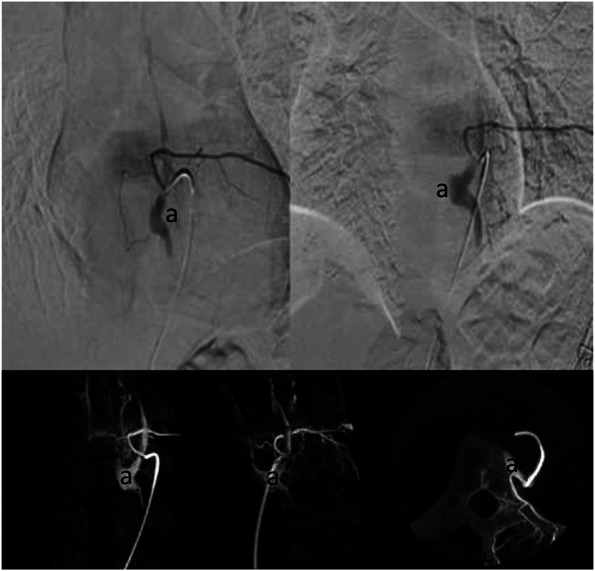

Clinical presentation: An adult patient who consulted about a 1 year and a half of flank pain refractory to analgesic management and hypoesthesia on palpation in the left T8 dermatome, therefore, pain of radicular origin was suspected. MRI of the thoracic spine was requested, showing an image suggestive of vascular malformation at the level of T8. After identification of the lesion, the patient was taken to spinal angiography to delimit the vascular malformation, finding an image suggestive of spinal venous vascular ectasia associated with a low-flow fistula of paravertebral location at T8. Subsequently, the case was discussed by a multidisciplinary team that established endovascular embolization as the best option for treatment. Thus, achieving complete occlusion of the lesion without complications and a slow improvement of the symptoms.

Conclusion: Spinal venous vascular ectasia associated with a low-flow fistula of paravertebral location is a very low-frequency entity that despite manifesting with myelopathy in some cases may generate radicular irritative symptoms and is differentiated from other lesions by its unusual location in spinal angiography.